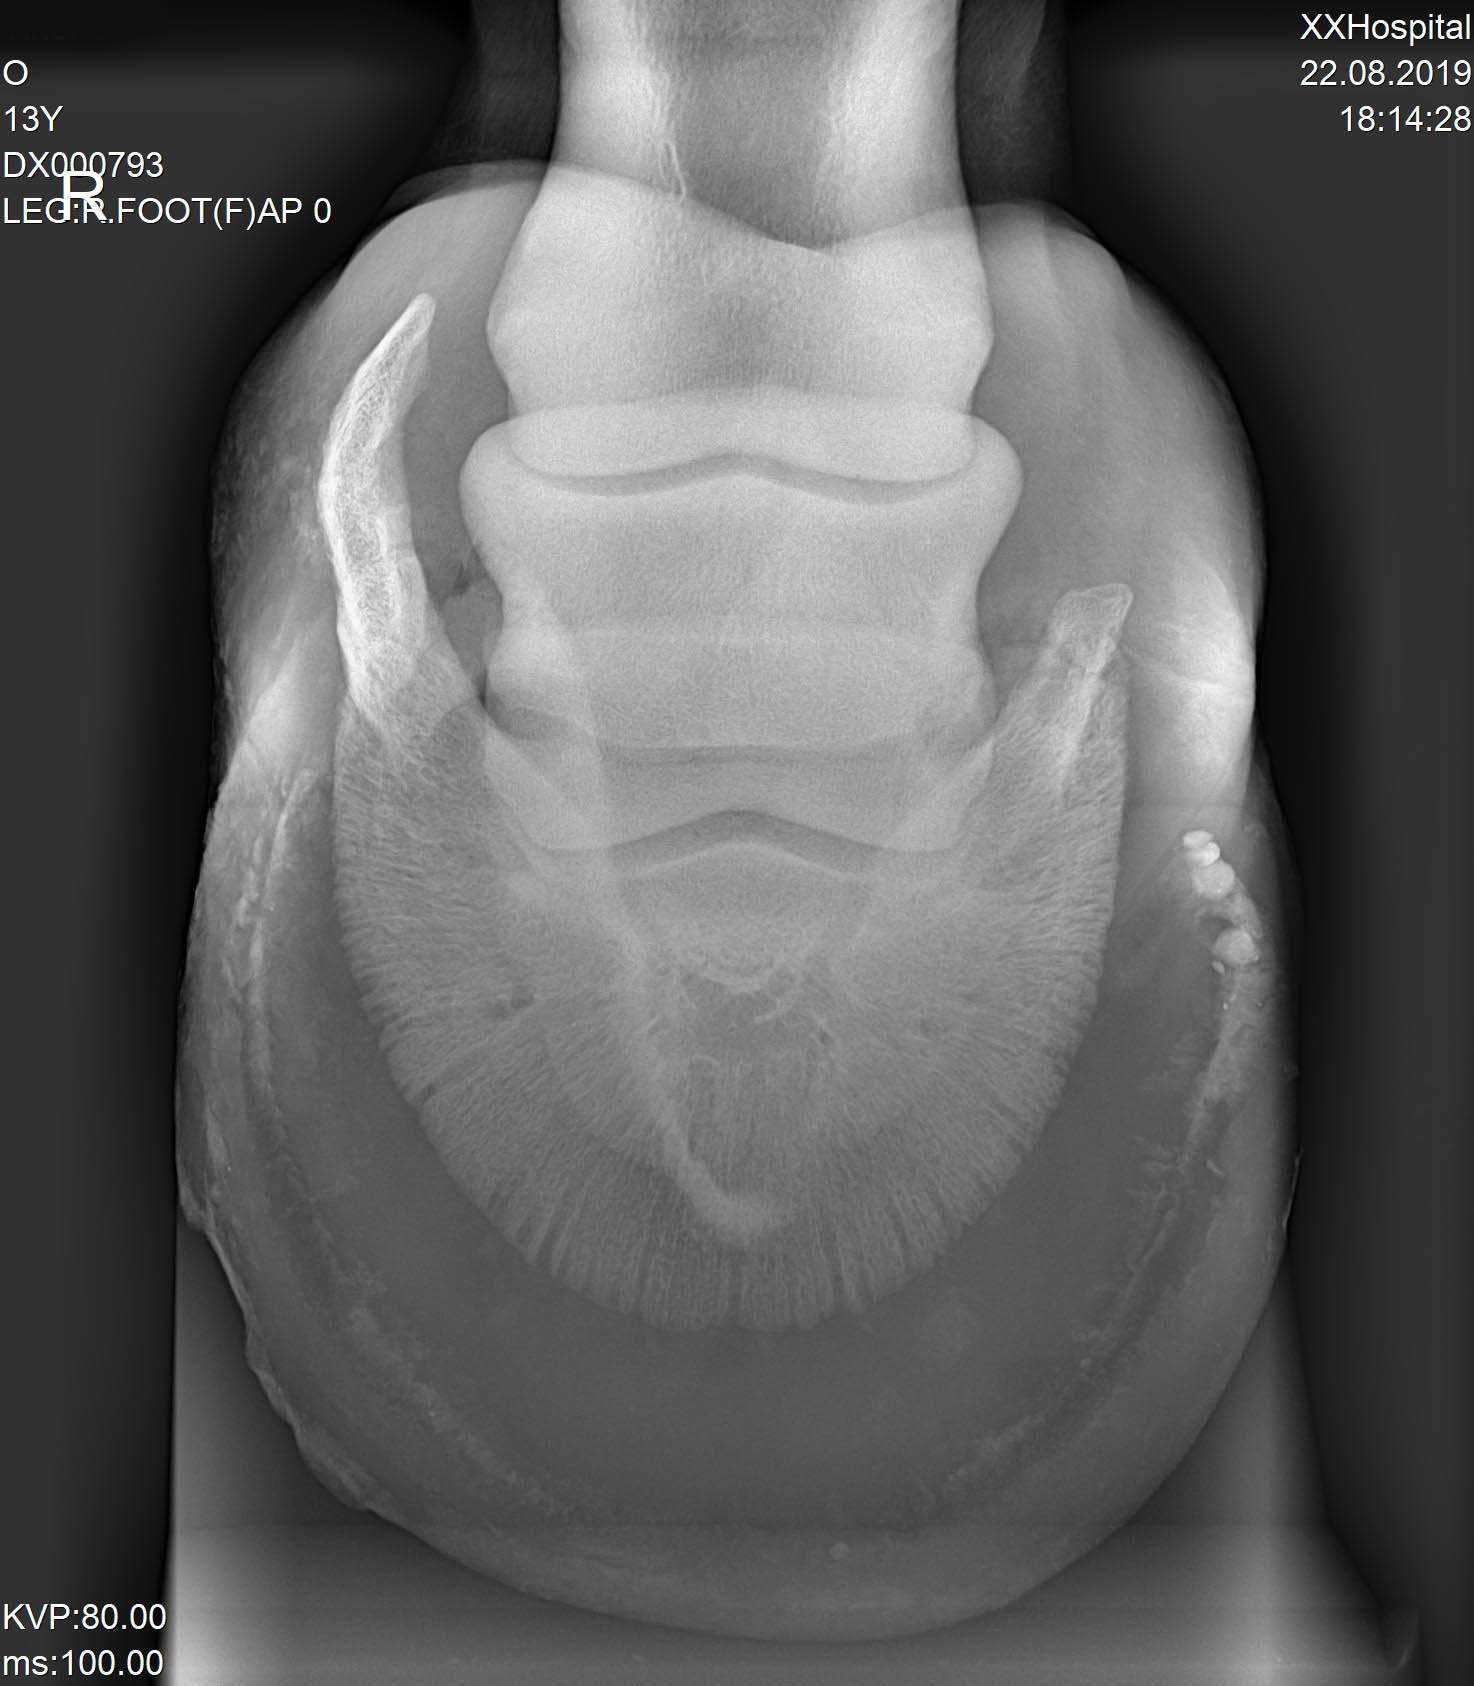

Результаты рентгенологического исследования:

Правая грудная конечность – оссификация латерального хряща копытной кости.

Левая грудная конечность – оссификация латерального хряща копытной кости.